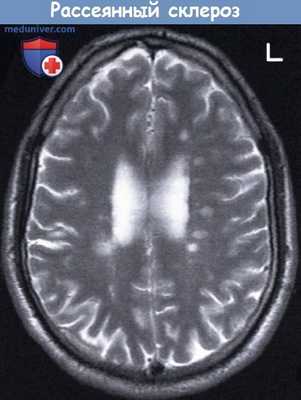

ж) Рассеянный склероз — самое распространенное заболевание нервной системы у молодых людей, проживающих в умеренных широтах по обеим сторонам от экватора. Рассеянным склерозом чаще болеют женщины; соотношение заболеваемости женщин и мужчин составляет 3:2. Дебют заболевания чаще всего приходится на возраст 30 лет, однако высокую заболеваемость отмечают в возрасте от 15 до 45 лет.

Рассеянный склероз—первичное демиелинизирующее заболевание (первоначально возникают бляшки рассеянного склероза—очаги демиелинизации белого вещества), однако могут также происходить демиелинизация серого вещества и потеря аксонов. При этом заболевании происходит дегенерация лишенных миелиновой оболочки аксонов, которая, вероятно, может быть связана с разрушением ионных натриевых каналов. Кроме того, нарушается проведение импульса по расположенным рядом миелинизированным нервным волокнам за счет отека вследствие образования воспалительного экссудата. Со временем происходит замещение очагов демиелинизации глиальной рубцовой тканью. При патологоанатомическом исследовании срезов мозга старые очаги демиелинизации характеризуются повышенной плотностью—склерозом.

Чаще всего первые очаги демиелинизации появляются в шейных отделах спинного мозга, верхней части ствола мозга, зрительном нерве, а также белом веществе, окружающем желудочки, и мозжечковом белом веществе. Рассеянный склероз не является системным заболеванием и не поражает избирательно определенные анатомические структуры; демиелинизации могут подвергаться участки смежных двигательных и чувствительных нейронов.

Т2-взвешенная МРТ мужчины 28 лет, аксиальная проекция.

Многоочаговая демиелинизация вследствие рассеянного склероза: очаги поражения белого вещества повышенной плотности.

В левой части мозга перивентрикулярно расположены, по крайней мере, пять очагов.

(Томограмма предоставлена Joe Walsh, врачом отделения радиологии университетской больницы, Голуэй, Ирландия.)

L—Левая сторона